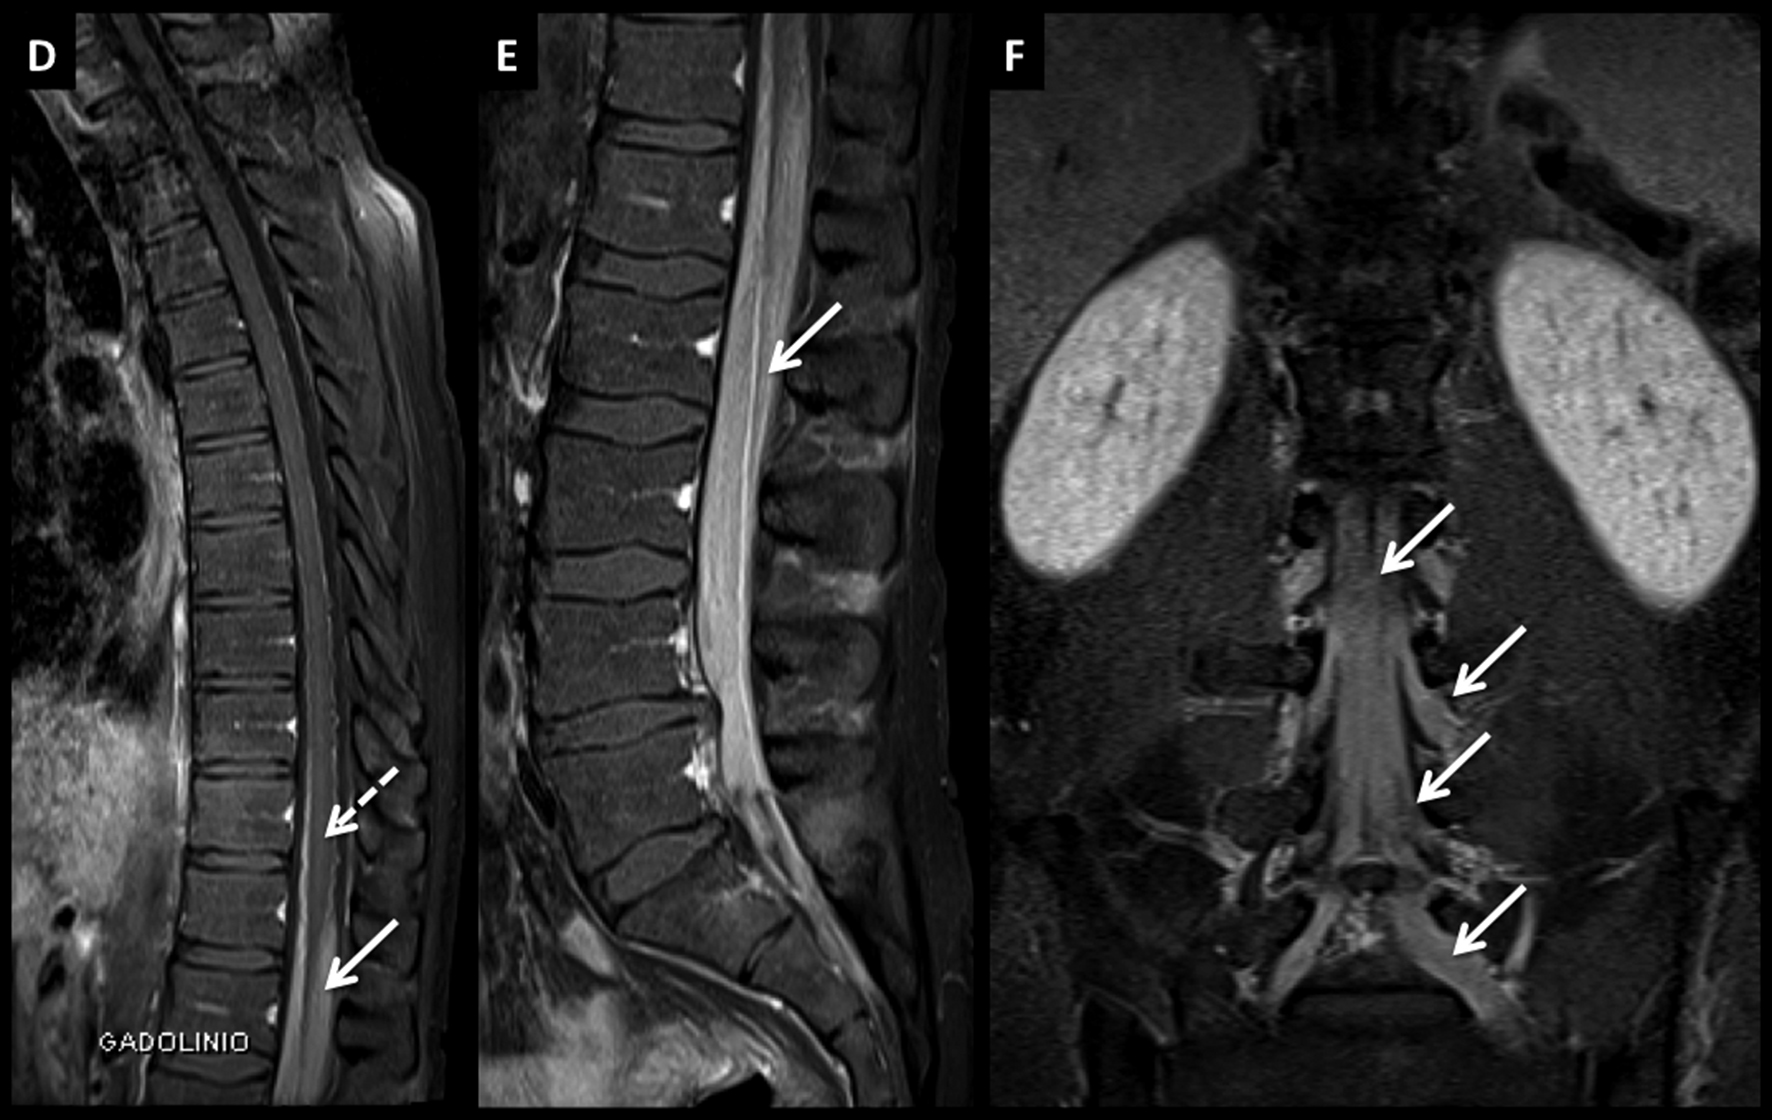

Figura 7

LNH, infiltración de cola de caballo, compromiso leptomeníngeo secundario.

Paciente joven con LNH y síndrome radicular asociado. En el estudio de estadificación se encuentra un patrón de infiltración de las raíces de la cola de caballo y se confirma el diagnóstico por estudio citológico del líquido céfalo raquídeo.

Este tipo de patrón se caracteriza por raíces nerviosas engrosadas que luego de administrar medio de contraste (D a F) presentan intenso realce.

El proceso infiltrativo rodea al cono medular (flecha discontínua) y puede contribuir a la clínica del paciente.